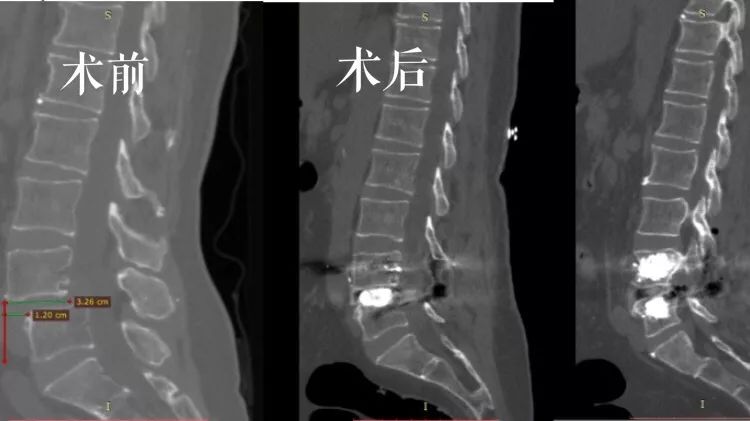

术前术后CT对比

术后CT示腰4-5椎间融合器固定在位,腰4/5椎体内骨水泥填充于螺钉周围,螺钉固定妥。

患者术后复查CT示骨水泥钉固定在位,腰4椎体复位良好,椎管减压充分!患者诉腰部及下肢疼痛明显减轻,四肢活动,肌力肌张力同术前!